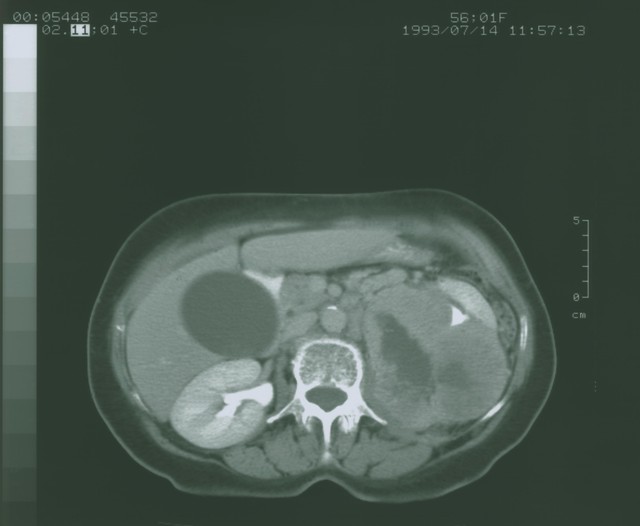

01第一种,肝囊肿:肝脏上的“小水泡”。

这是体检中最常见的肝脏良性异常,每10个做腹部B超的人里,就有1-2人查出肝囊肿。多为先天性发育异常,是肝脏内包裹清亮无菌液体的囊腔,无病毒、无癌细胞,不损伤肝细胞、不恶变,生长极缓慢,如同肝脏上的“安静小痣”。单纯性肝囊肿尸检检出率0.16%-0.19%,95%以上的小囊肿终生无需治疗,直径(一般小于5厘米)就不用担心,过大或有压迫症状者需干预。- 应对建议:每年1次B超复查,无需吃药、手术;避免剧烈撞击腹部即可。